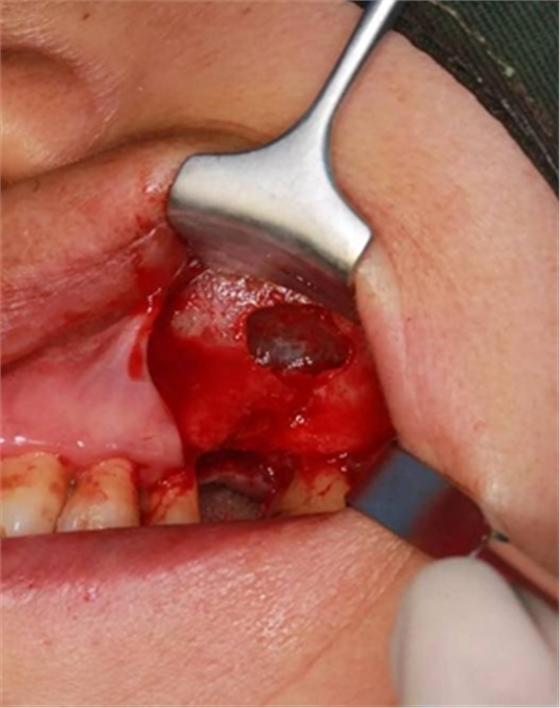

六個月之后